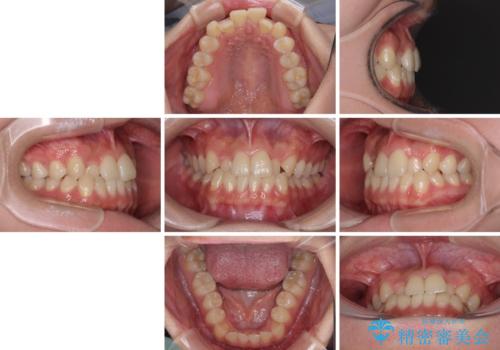

前歯のクロスバイトを短期間で解消 目立たないワイヤー矯正

- 前歯のクロスバイトを治したいとのことで来院された患者様です。

できる限り楽して、短期間で治したいとのことで、ワイヤー装置にて矯正治療を行うこととしました。